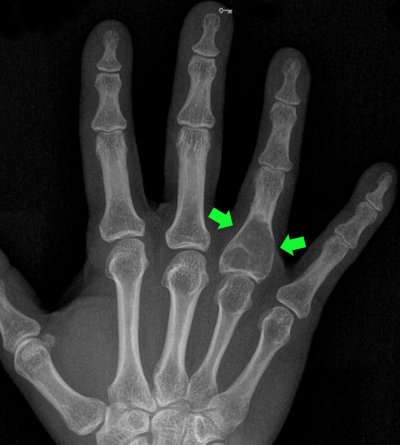

Kemiğin içinde kıkırdak kökenli tümörler de gelişebilir. Bunların bazıları küçük olup tedavi değil ama takip gerektirir. Bazıları ise daha büyük olur ve ameliyat ile tedavi edilmeleri gerekir. Enkondromlar kıkırdak kökenli kemik tümörleridir. Yani kemiğin içinde gelişen kıkırdağımsı tümörlerdir. (resim-8)

Düşük olasılıkla malign dönüşüm gösterebilme olasılıkları da vardır. Zaman zaman künt ağrılara neden olabilirler. Bu durumda ameliyatla temizlenmeleri gerekir. Enkondromlar ayrıca el kemiklerinde en fazla görülen tümörlerdir. Hasta bunun çoğu zaman farkında olmayabilir. Kemiğin içinde gelişip ‘korteks’ dediğimiz kemik duvarlarını aşırı derecede inceltebilir. Bu durumda çok basit bir travmayla bile kemikte kırık meydana gelebilecektir. Bazen ameliyatsız iyileşme olabileceği gibi bazen de ameliyat endikasyonu doğar. (resim-9)